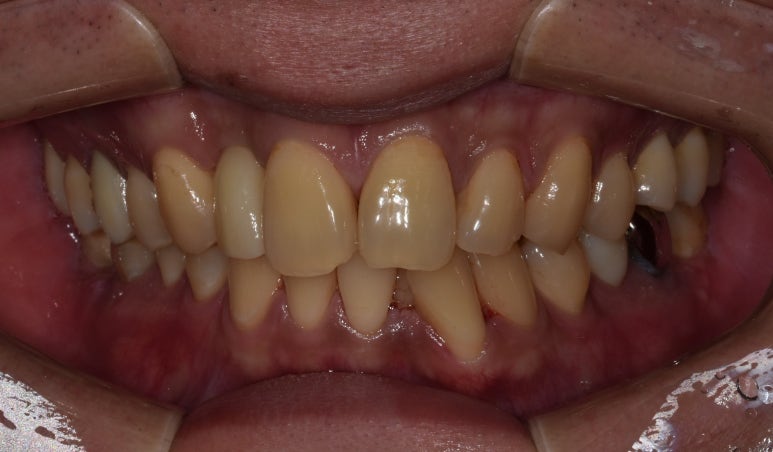

20대임플란트 실제 사례

25세 여성

(전) 2022-03-03 (후) 2022-10-11